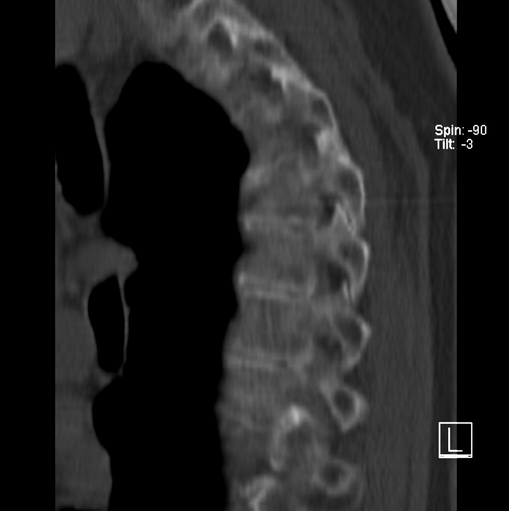

标题: CT25377:脊柱有无压缩骨折?

女、73、胸痛、胸闷3个月,无明显外伤病史,x线疑t4、t7陈旧压缩骨折,ct未经明显骨折,请问结论如何报?

老年女性病人,骨质稀疏,有些驼背,t4明显变扁,t7略变扁,椎体边缘无中断,骨小梁排列正常,无嵌插所致致密线。结合无明显外伤史,考虑老年骨质稀疏,慢性压缩改变,正如老年人骨质稀疏椎体呈双凹改变一样。我考虑报:老年骨质稀疏,t4、t7楔形变,脊柱曲度改变(驼背).敬请大家指教。

1)多个胸椎陈旧性压缩性骨折。2)胸椎普遍性骨质疏松。3)胸椎退行性改变。